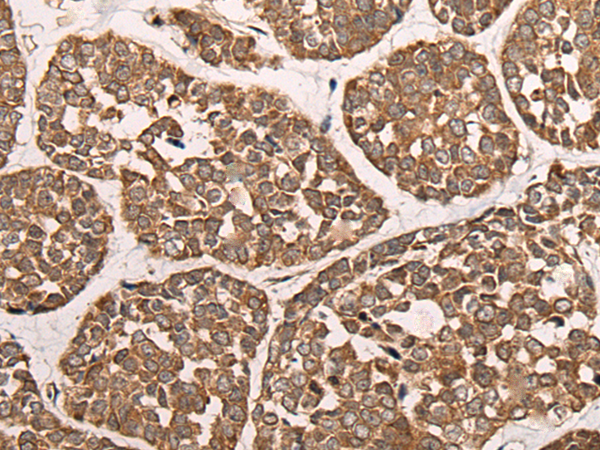

IHC positive control: |

Human liver cancer and human esophagus cancer |